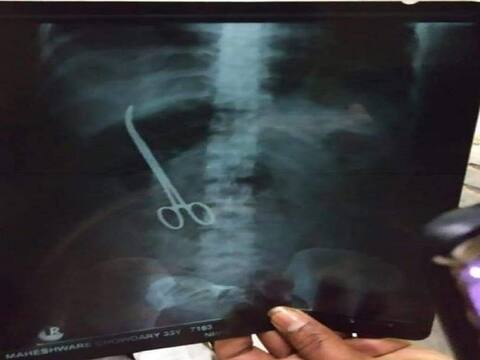

हैदराबाद: डॉक्टर वैसे तो भगवान के रूप होते हैं लेकिन कई बार उनकी लापरवाही की खबरें भी सुनने में आती है. ऐसा ही एक मामला अब हैदराबाद से सामने आया है जहां डॉक्टरों ने सर्जरी के दौरान महिला के पेट में कथित तौर पर एक कैंची छोड़ दी. शहर के एक सरकारी अस्पताल के डॉक्टरों की एक टीम के खिलाफ शनिवार को मामला दर्ज किया गया. एक व्यक्ति ने शिकायत की है कि उन्होंने पिछले साल नवंबर में एक सर्जरी के दौरान उसकी पत्नी के पेट में एक कैंची छोड़ दी थी. पुलिस ने बताया कि कथित चिकित्सा लापरवाही का मामला शुक्रवार को उस वक्त सामने आया, जब 33 वर्षीय महिला अपने पेट में दर्द महसूस करने के बाद अस्पताल गई और एक एक्स-रे करवाया. पुलिस ने आगे बताया कि जीवन या व्यक्तिगत सुरक्षा को खतरे में डाल नुकसान पहुंचाने के आरोप में डॉक्टरों की एक टीम के खिलाफ मामला दर्ज किया गया है. यह भी पढ़ें-सीबीआई की कोलकाता पुलिस कमिश्नर राजीव कुमार से पूछताछ जारी, आधे घंटे बाद वकील को CBI कार्यालय से बाहर जाने कहारॉबर्ट वाड्रा से आज 3 घंटे तक ED ने की पूछताछ, आर्म्स डीलर संजय भंडारी से कनेक्शन को लेकर पूछे गए सवालयूपी-उत्तराखंड में जहरीली शराब से मरने वालों की संख्या 77 तक पहुंची, चूहे मारने की दवाई मिलाने का है शक'फायर', 'अर्थ' और 'वाटर' जैसी फिल्म बनाने वाली दीपा मेहता को मिलेगा लाइफटाइम अचीवमेंट अवार्ड